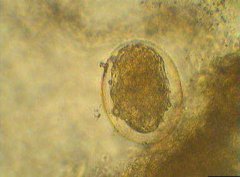

酒精性肝硬化是西方國(guó)家及地區(qū)肝硬化的常見(jiàn)病因。病理特征為大小基本一致的小結(jié)節(jié)型肝硬化。

②酒精性脂肪壞死,被稱為酒精性肝炎。顯微鏡下可見(jiàn)不同程度的脂肪壞死、mallory小體及急性炎癥和(或)細(xì)胞周?chē)w維組織增生。傳統(tǒng)觀點(diǎn)認(rèn)為酒精性肝炎是酒精性肝硬化的先兆。